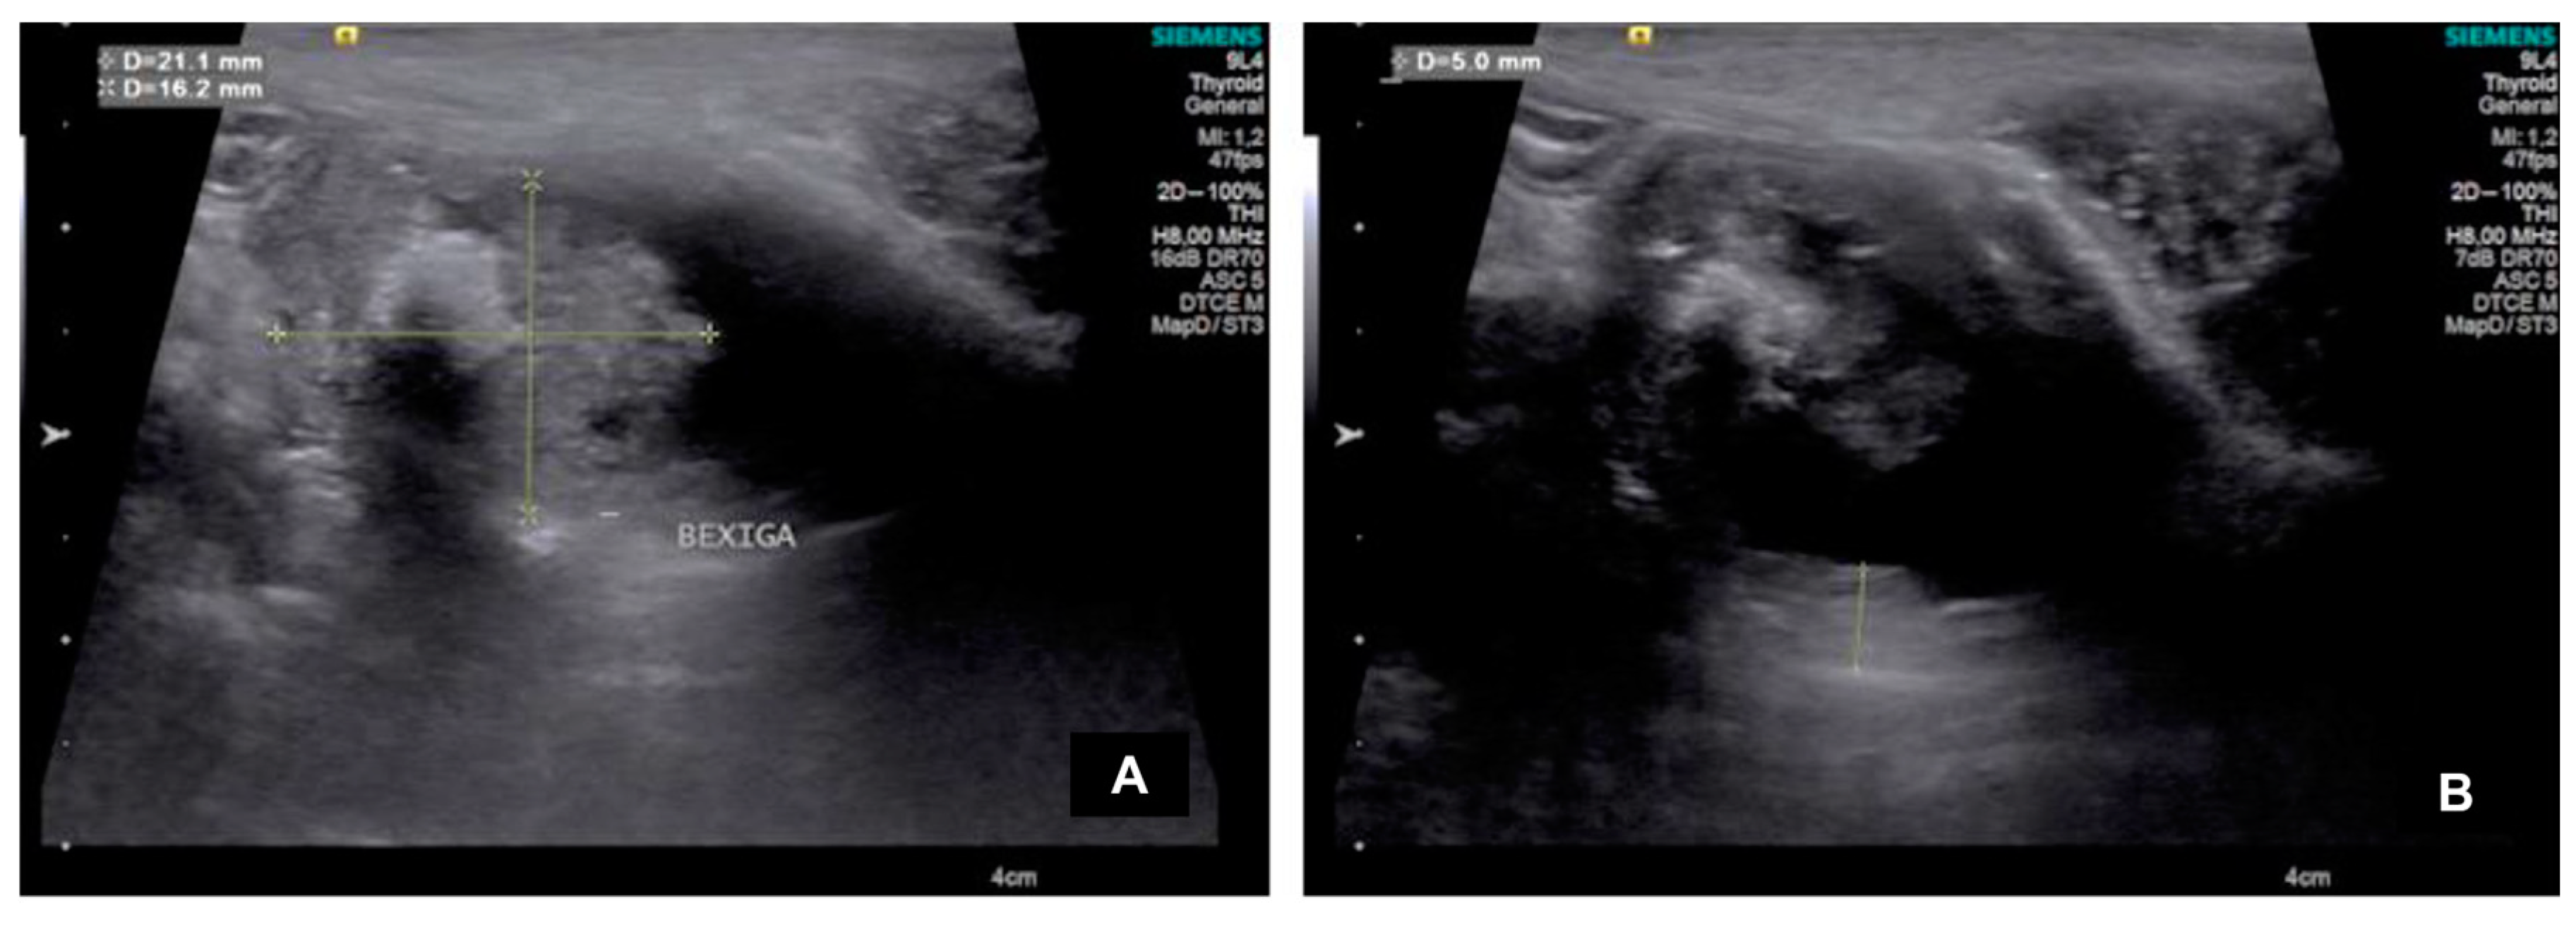

| Dog | Height (cm) | Length (cm) | Echotexture | Echogenicity | Location |

| 1 | 0.88 | 3.53 | Heterogeneous | Mixed | Dorsal |

| 2 | 2.76 | 4.49 | Heterogeneous | Hyperechogenic | Ventral, trigone e prostatic urethra |

| 3 | 1.62 | 2.11 | Heterogeneous | Hyperechogenic | Cranial (ventrodorsally) |

| 4 | 3.75 | 3.63 | Heterogeneous | Mixed | Cranial (ventrodorsally) |

| 5 | 0.60 | 1.41 | Homogeneous | Hyperechogenic | Trigone |

| 6 | 1.24 | 2.51 | Heterogeneous | Hyperechogenic | Dorsal |

| 7 | 1.19 | 3.87 | Heterogeneous | Hyperechogenic | Ventral |